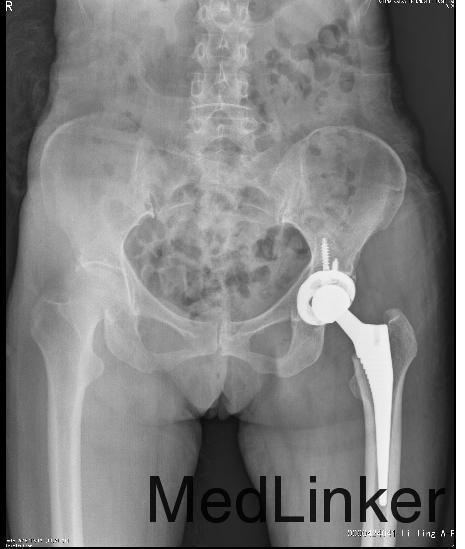

诊断:左侧股骨颈骨折(Garden Ⅳ型) 治疗:行左侧全髋关节置换术

术后患者恢复良好,术后一周出院,术后三个月回院复查,未发生髋关节脱位等并发症。